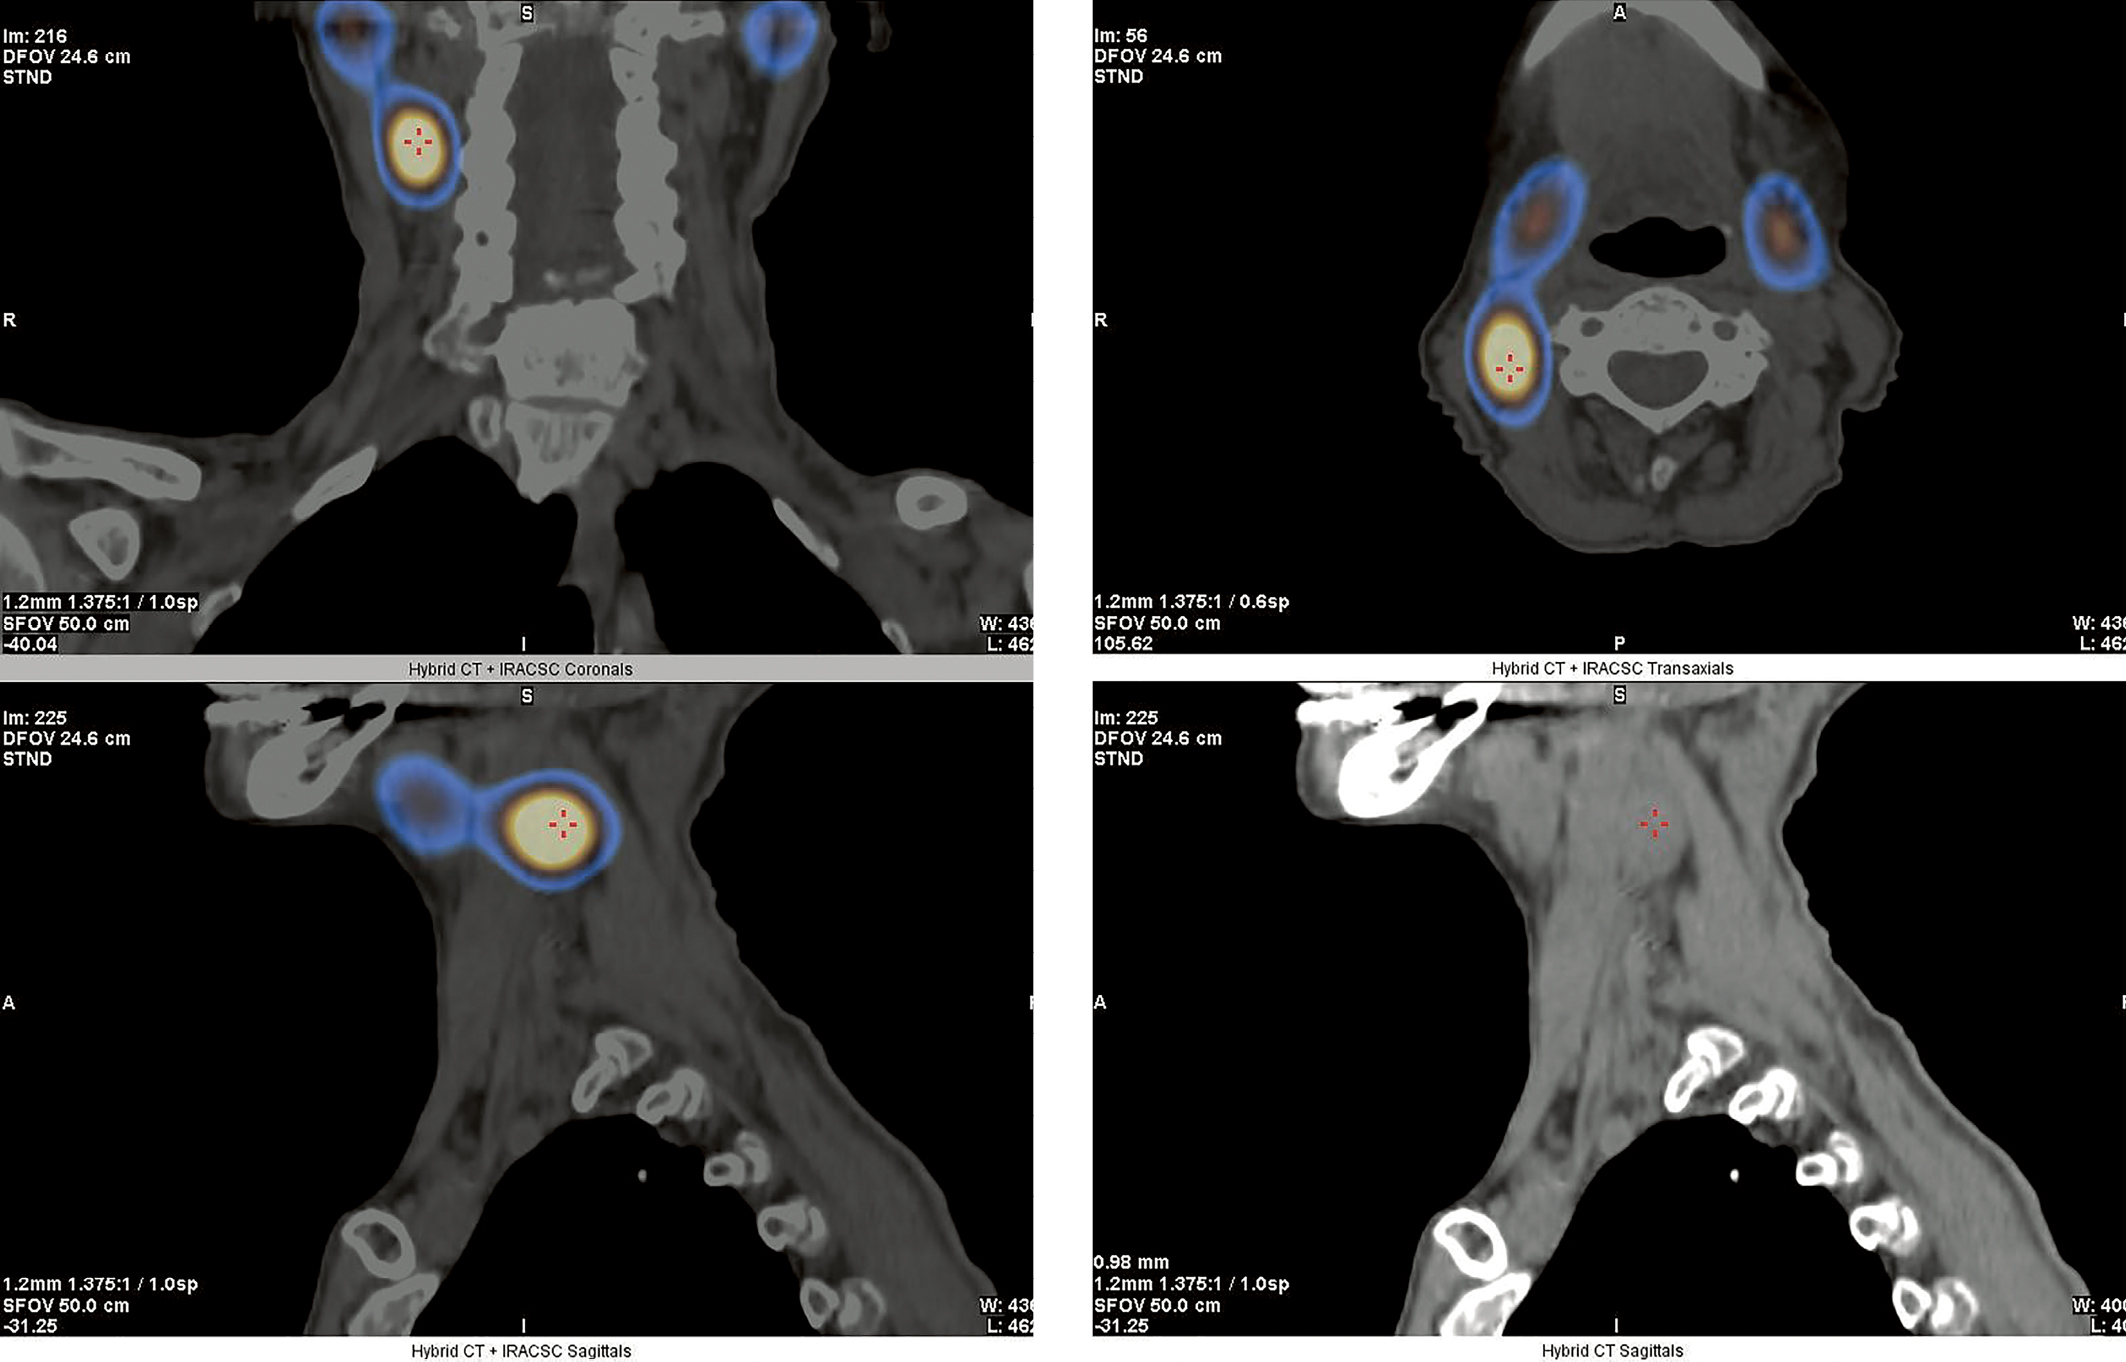

Объемное образование подтверждено в ходе проведения мультиспиральной компьютерной томографии (МСКТ) шеи с контрастным усилением (рис. 2).

Рисунок 2. МСКТ шеи с контрастным усилением от декабря 2021 г.

Стрелками отмечено атипично расположенное образование ОЩЖ.

Пациентка была осмотрена эндокринным хирургом, при пальпации в проекции образования отмечался кашель, что могло указывать на расположение опухоли вблизи возвратного гортанного нерва.